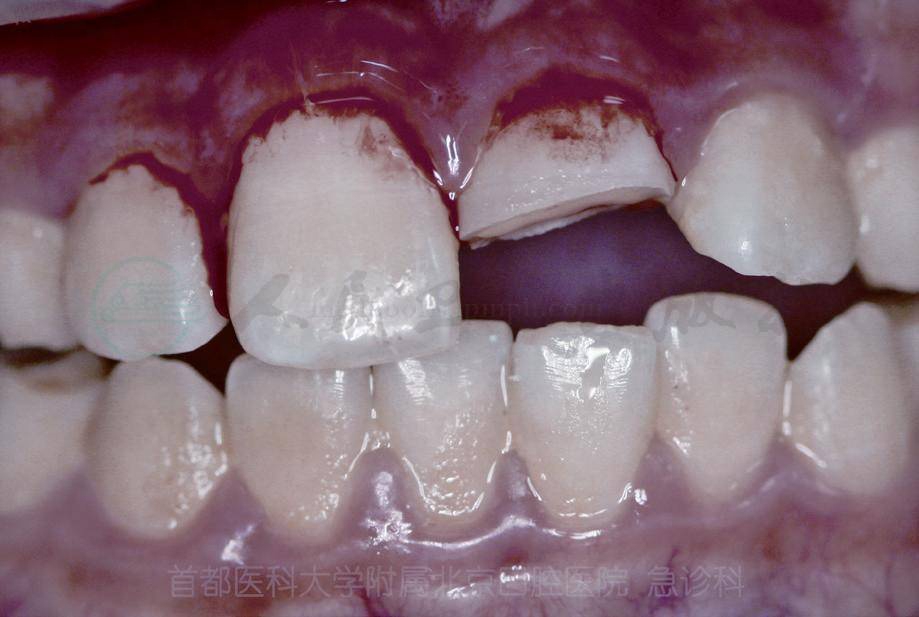

另外,牙半脱位性损伤可单独发生,也可同时伴随其他类型牙损伤。牙半脱位同时伴有冠折;也可以同时伴有根折,通过X线检查确诊(图5)。

A 牙半脱位伴有冠折

B 牙半脱位伴有根折

C 牙半脱位伴有根折X线片

图5 牙半脱位伴有其他损伤